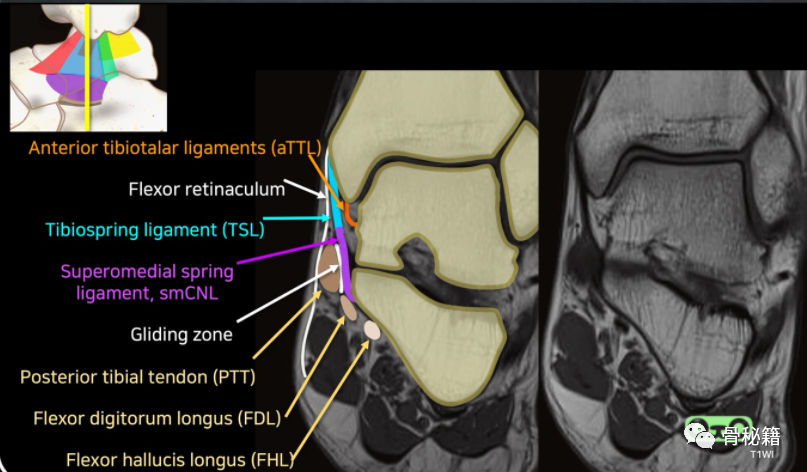

韧带由两层组成。浅层具有可变附件并穿过两个关节,而深层具有距骨附件并穿过一个关节:

它是一条牢固的三角带,附着于内踝的顶点和前后缘。足底跟舟韧带可以被认为是内侧韧带复合体的一部分。

• 表层:从前到后

通过后外侧到距骨的内侧及其内侧结节,向前传至舟骨结节,

• 在舟骨结节后与足底跟舟韧带的内侧边缘融合

• 浅层是由多个分束组成的宽阔三角形结构。它是三角肌复合体中最薄弱的一层。该层公认的组成部分是胫舟韧带 (TNL)、胫弹簧韧带 (TSL) 和胫跟韧带 (TCL)。所有这三个束都与弹簧韧带复合体 (SL) 的上内侧部分融合。

• 胫舟韧带 (前)

• 胫弹簧韧带

• 胫跟韧带 (中间)

• 浅表后胫距韧带 (后)

• 深层: 这一层在关节内,被滑膜覆盖

从内踝到距骨的大而强韧的韧带被浅表后胫距韧带 和胫跟韧带覆盖韧带短而细,起自内踝尖,止于距骨内侧面的非关节部,由胫骨后肌腱和趾长屈肌腱穿过。

前胫距韧带 (ATTL)

深后胫距韧带 (DPTTL)

• 三角韧带复合体深层的成分。三角韧带的深层由小且可变的前胫距韧带 (ATTL) 和非常强壮的后胫距韧带 (PTTL) 形成。